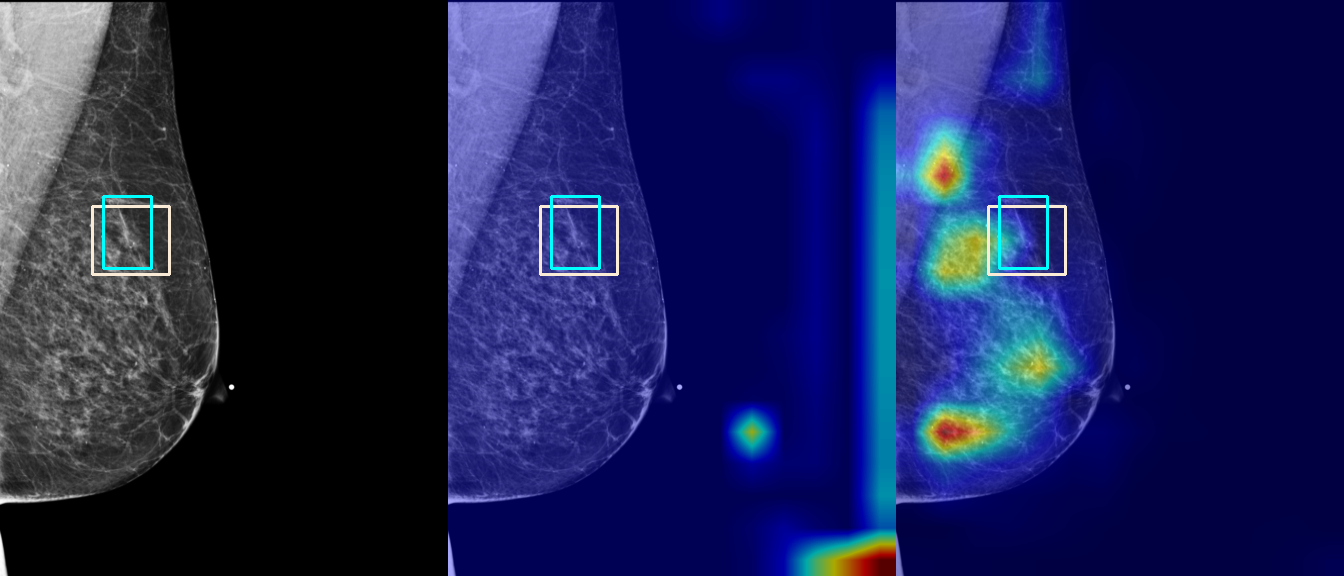

To interpret the decision-making process behind the quantitative results, we visualized Class Activation Maps (CAM) for the top-performing methods, ERM and VREx. Figures 1 through 2 illustrate discriminative regions identified by the models within the full mammograms.

Localization of Clinical Features: A key concern in medical AI is whether high performance stems from genuine pathology detection or spurious background correlations. Our visualizations suggest that Standard ERM achieves its superior quantitative performance by predominantly prioritizing clinical cues. As shown in the top rows of the Figure 1 and Figure 2, the ERM-trained models consistently focus attention on the specific lesion regions within the breast tissue. This demonstrates that despite lacking explicit invariance constraints, ERM is capable of learning robust, medically relevant features when trained on diverse multi-source data.

Attention Drift in Both Methods: While both ERM and VREx generally identify the correct region of interest in successful cases, neither method is immune to attention drift. We observe instances in both training paradigms where the model focuses on irrelevant areas, such as healthy fibroglandular tissue or background artifacts (e.g., rows 5 and 6 in Figure 1). This indicates that while VREx is designed to penalize instability, it does not guarantee perfect anatomical focus compared to the unconstrained ERM baseline.